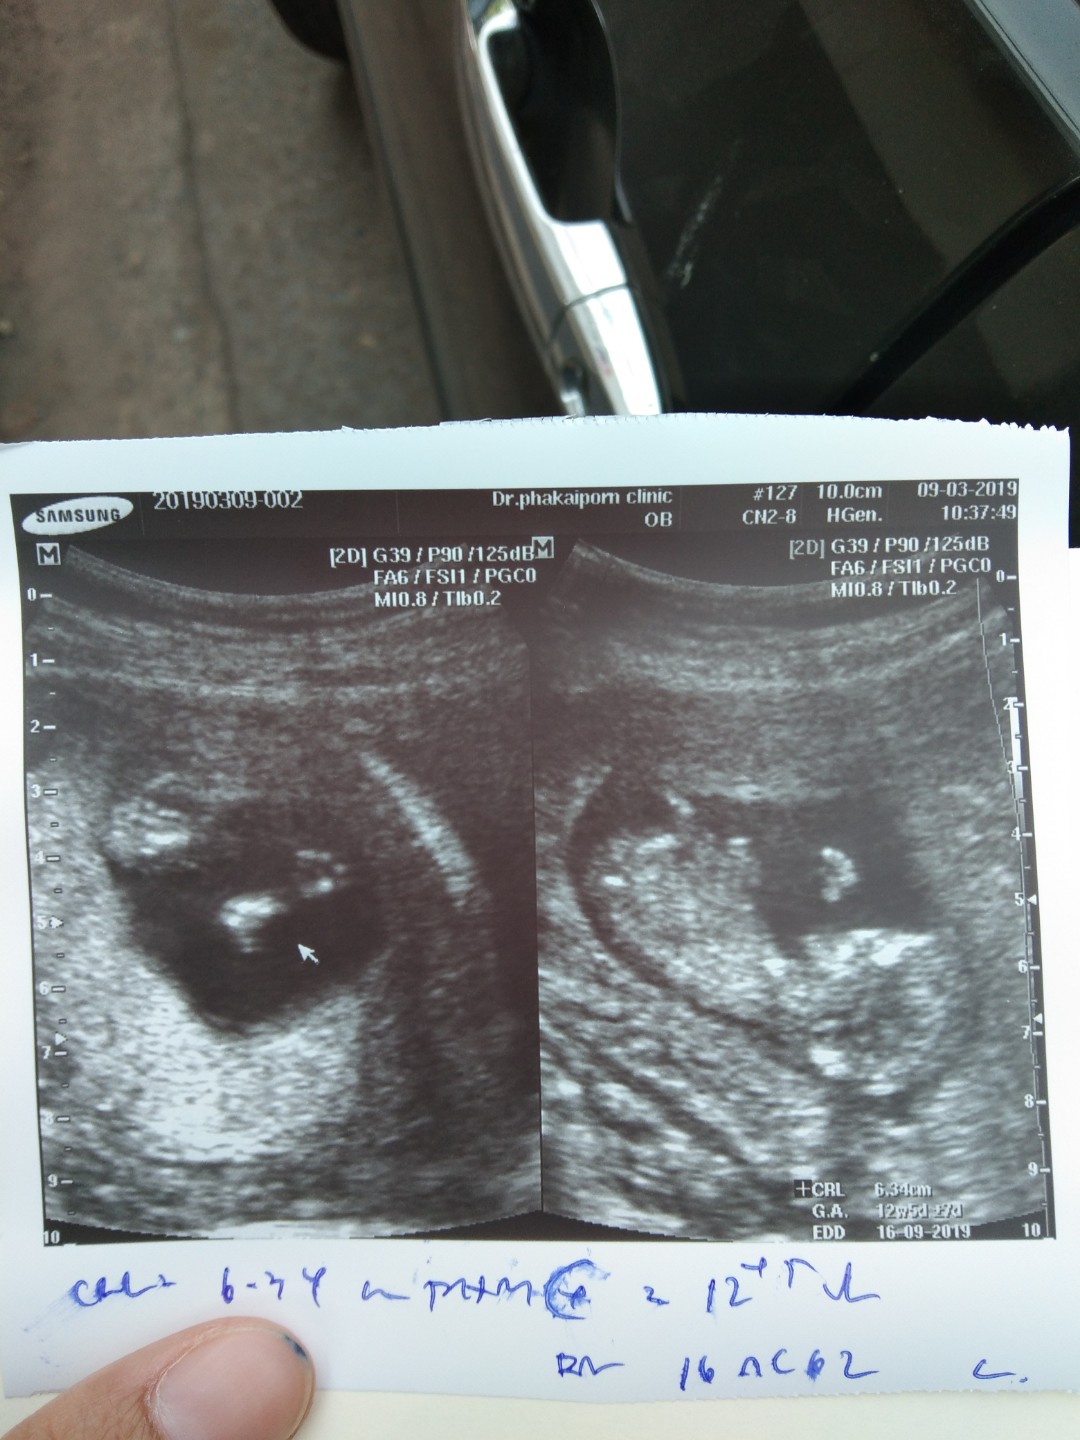

12w1d ค้า

ตอน 12. Week